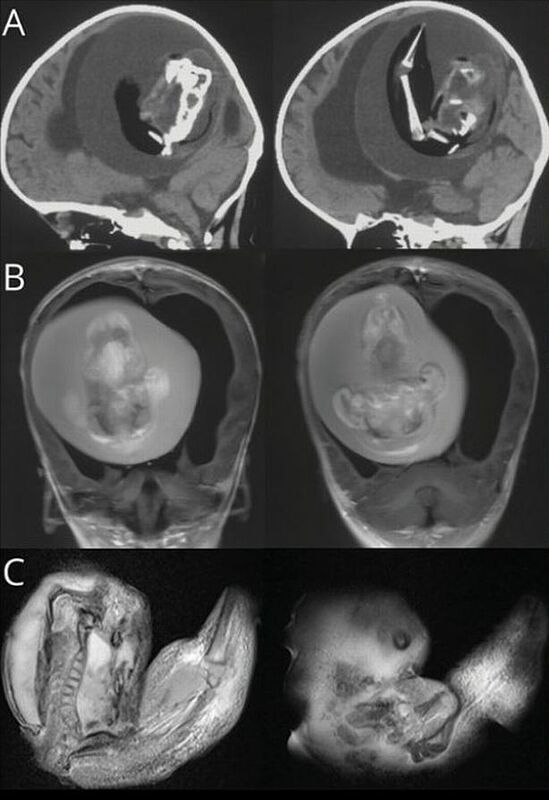

Khi thấy bé gái một tuổi đầu phình to bất thường, có vấn đề về kỹ năng vận động, khi được đưa đến bệnh viện chụp CT cho thấy một bào thai sống đang đè lên não của bé.

Bác sĩ Bệnh viện Hoa Sơn, Đại học Phúc Đán, nhận định ban đầu đây là một cặp song sinh nhưng vì lý do nào đó một thai nhi đã phát triển và bao bọc người chị em của mình. Bào thai trong đầu của bé gái tiếp tục phát triển nhiều tháng như khi còn trong bụng mẹ, đã có chi trên, xương và móng tay.

Gia đình không phát hiện tình trạng này trong vòng một năm sau khi bé chào đời, chỉ nhận thấy điểm bất thường khi đầu em trở nên quá lớn, không thể hoạt động bình thường. Bé cũng bị não úng thủy - tình trạng tích tụ chất lỏng trong não khiến đầu to ra, mệt mỏi cực độ và co giật.

Các bác sĩ đã phẫu thuật để loại bỏ bào thai trong đầu của bé. Tuy nhiên, do tổn thương lâu dài, họ chưa chắc chắn liệu em có thể sống sót hay không.

"Thai nhi trong hộp sọ sinh ra từ các phôi nang chưa thể tách rời. Các phần dính liền phát triển thành não trước của bào thai vật chủ, bao bọc phôi khác trong quá trình gấp tấm thần kinh", bác sĩ Zongze Li, bác sĩ thần kinh điều trị cho bé gái, giải thích.

Ảnh chụp CT bào thai sống trong não bé gái.

Bác sĩ cho biết thai trong thai là hiện tượng cực kỳ hiếm gặp, thế giới chỉ ghi nhận 200 ca, trong đó 19 trường hợp bào thai cư trú ở não. Hội chứng này cũng xảy ra ở xương chậu, miệng và bộ phận sinh dục.

Thai nhi song sinh có thể phát triển nhiều tháng bên trong cơ thể người chị em, có cả cơ quan và tứ chi. Tình trạng này thường xảy ra ở các cặp song sinh cùng trứng, không thể tách rời hoàn toàn trong bụng mẹ. Đến nay, các nhà khoa học chưa biết rõ nguyên nhân dẫn đến hiện tượng kỳ lạ này.